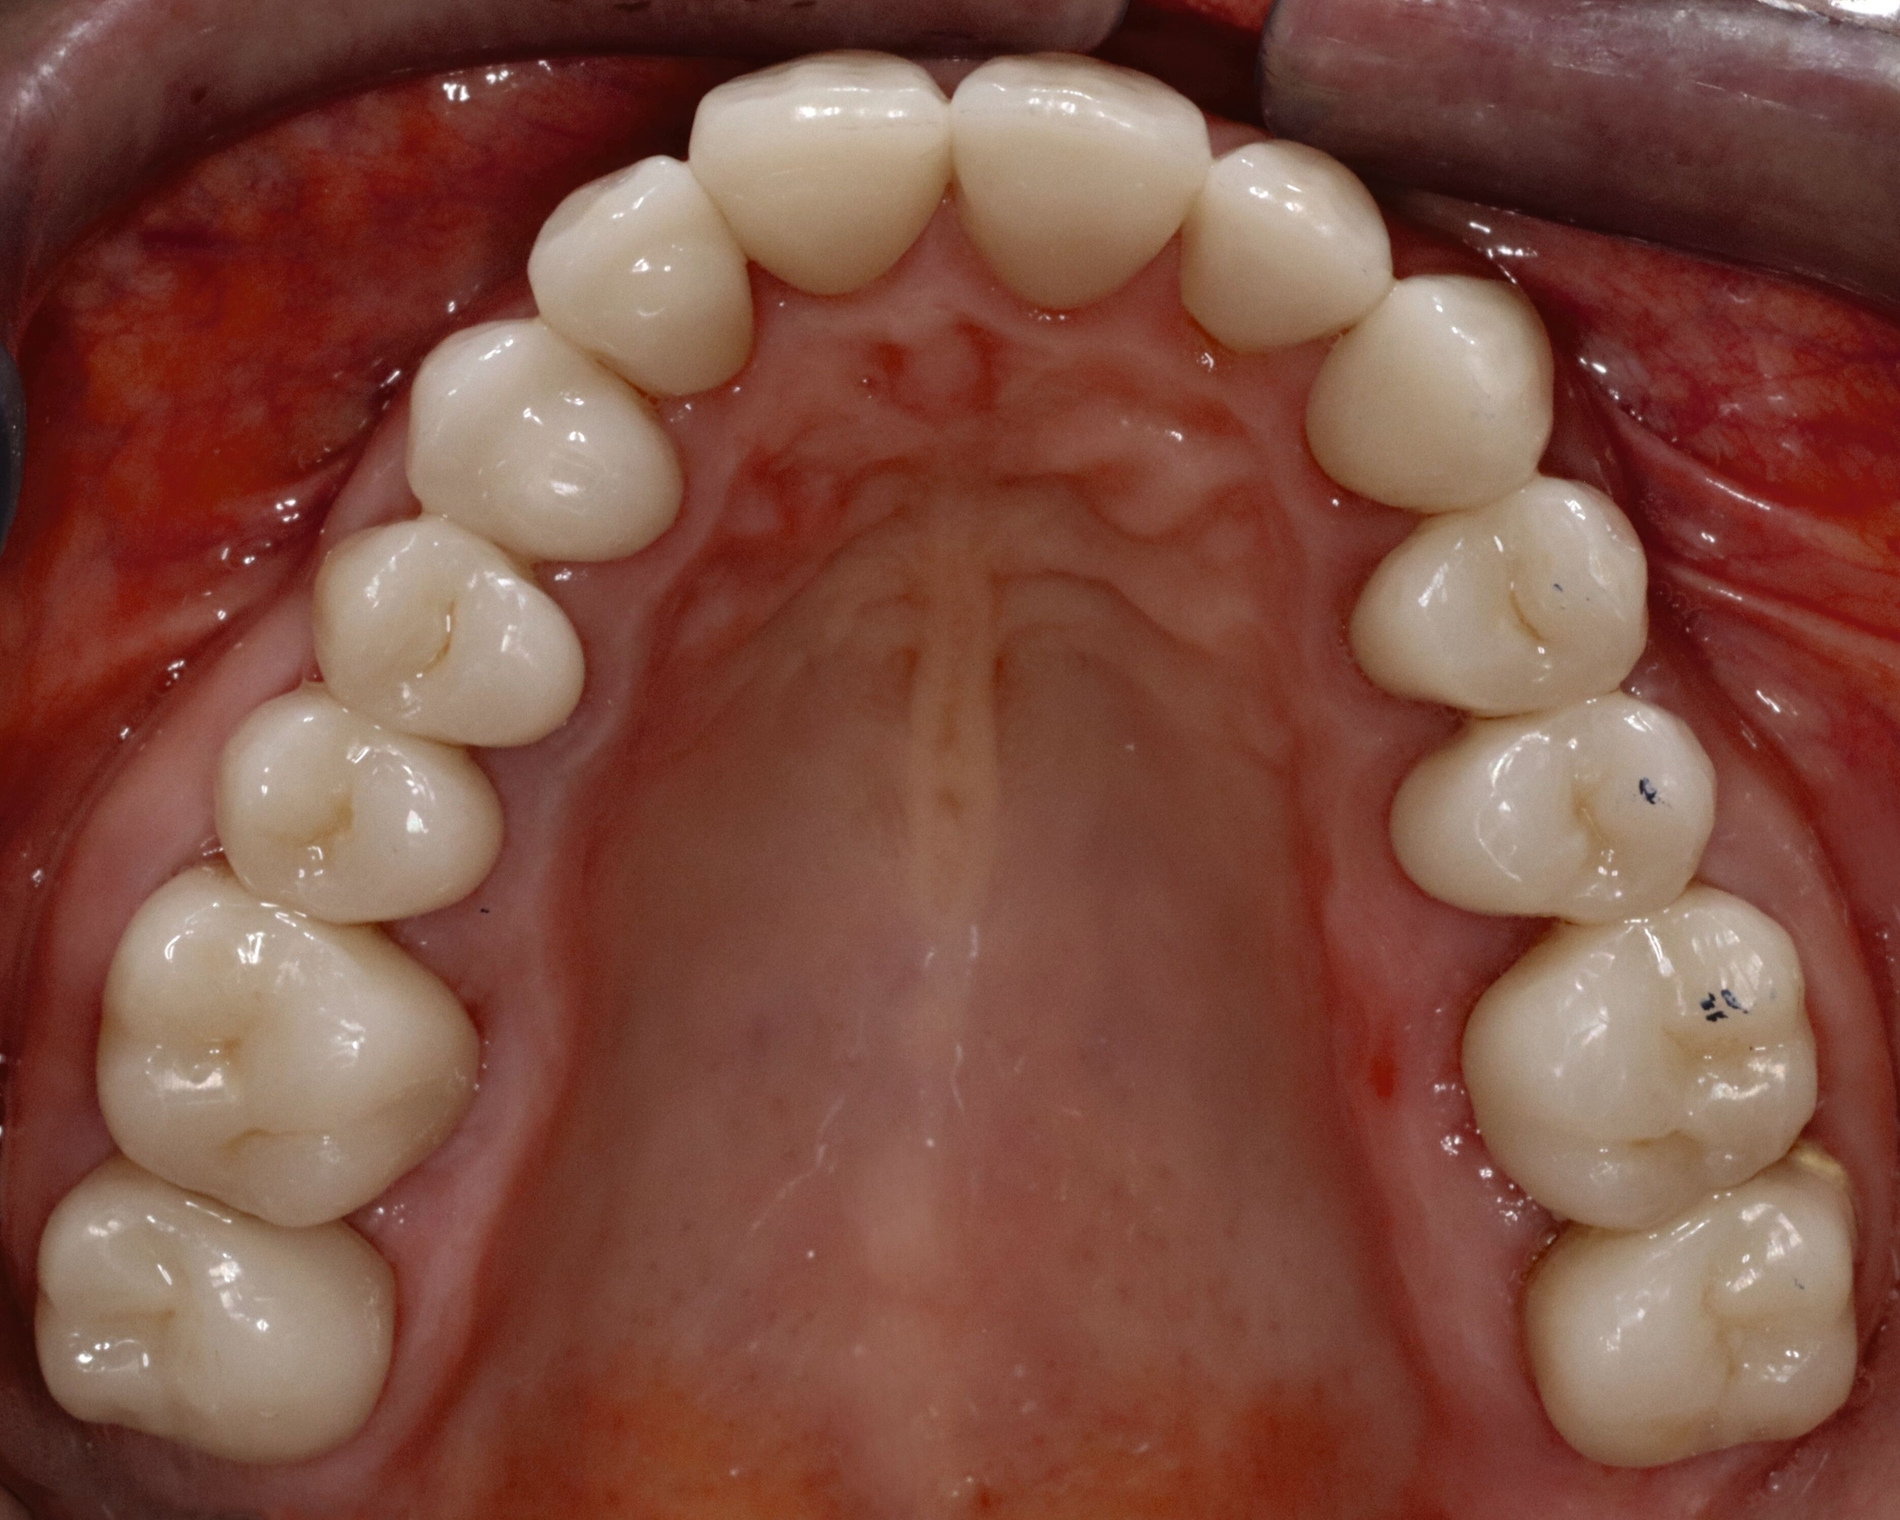

In der extraoralen Untersuchung zeigte sich ein trockenes Hautbild ohne weitere Auffälligkeiten. Intraoral waren multiple initiale Läsionen, eine erhöhte Plaqueakkumulation, sowie diverse Kompositrestaurationen im Seitenzahnbereich auffällig (Abbildungen 2a und 2b).

Eine 62-jährige Patientin stellte sich im Jahr 2025 in der CMD-Sprechstunde vor. Gemäß der allgemeinen Anamnese bestanden keine Vorerkrankungen. Die spezielle Anamnese zeigte den Zustand nach alio loco erfolgter prothetischer Rekonstruktion im Dezember 2024 mit festsitzendem Zahnersatz. Die Versorgung umfasste 14 Kronenrestaurationen (17–27) im Oberkiefer sowie zwölf Kronen (45–36) und zwei Implantatsuprakonstruktionen (046, 047) im Unterkiefer.